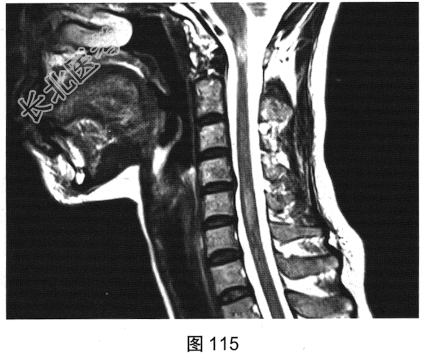

- 多项选择题2.[提示]患者行脊柱MRI检查,如图115~图120所示。患者MRI检查可见哪些阳性影像学表现( )

A、T2WI示颈髓和胸髓病灶呈高信号

B、增强扫描颈髓病灶多发斑片状强化

C、横断面增强扫描脊髓侧索病灶强化

F、T1WI示颈髓病灶呈等信号